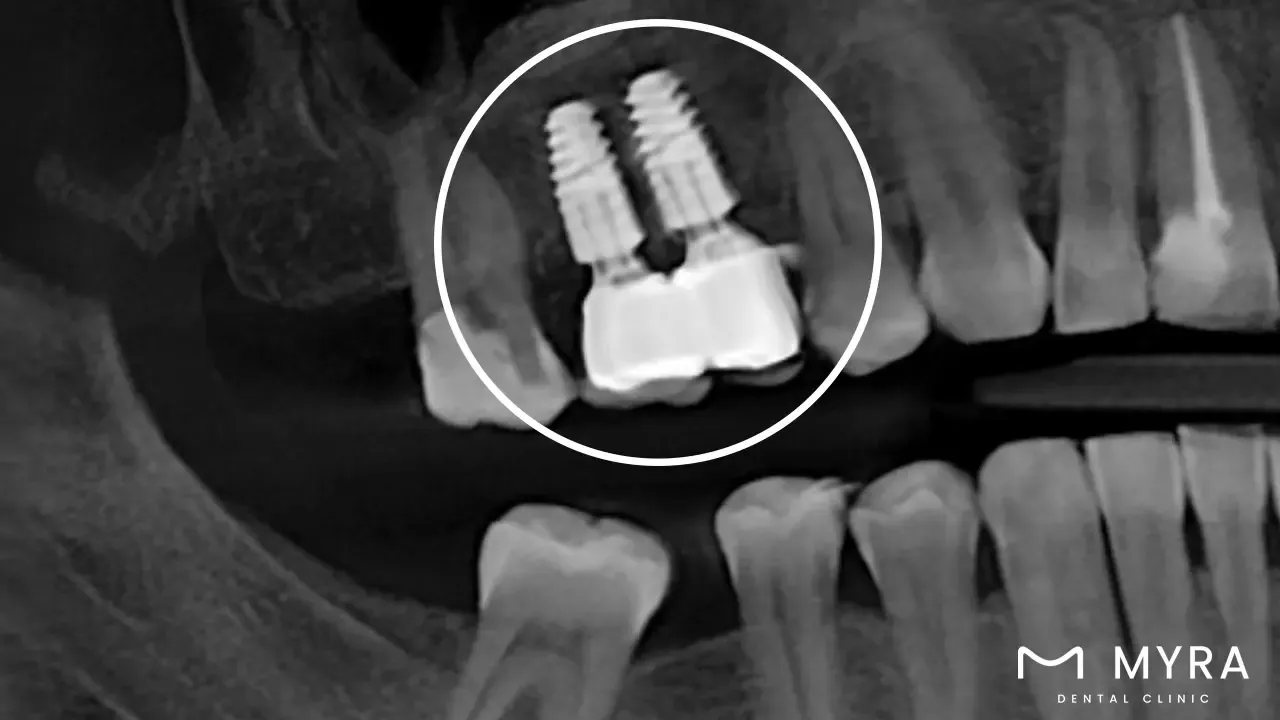

A form of dental implant called a multiple-tooth implant is utilized to insert an absent tooth or teeth. These techniques involve the surgical insertion of more than one dental implant supporting a dental bridge or denture on the jawbone, offering a safe and effective substitution for numerous lost teeth. The implants uphold the denture or dental bridge that has synthetic tooth roots and is constructed of biocompatible materials, for example, titanium. Multiple tooth implants are an effective long-term approach to substitute absent teeth with the purpose of resembling the appearance and functionality of real teeth closely. The method entails a thorough examination by a dental expert, placing the implants through surgery, followed by attaching a dental bridge or denture to the implants.

The method includes the medical positioning of two or more dental implants within the jawbone, which help as artificial tooth roots to assist a dental bridge or denture. The implants are built of biocompatible stuff for example titanium and are designed to merge with the bone after some time in a method called osseointegration. A dental bridge or denture is joined to the implants after they have integrated with the bone, which delivers a secure and operative substitute for the absent teeth.

A multiple tooth implant is a dental implant procedure designed to replace two or more missing teeth. This treatment involves the surgical placement of dental implants into the jawbone, which serve as anchors to support a dental bridge or denture. The implants provide a stable and secure foundation for the prosthetic teeth, allowing for improved chewing function, speech, and aesthetics. The number of implants required will depend on the specific case and the number of missing teeth being replaced. The average cost of multiple tooth implants can range from £1600 up to £4000, depending on factors such as the number of implants needed, the complexity of the case, the type of restoration used, and any additional treatments required. It is important to consult with a dental professional to determine the exact cost based on individual circumstances.